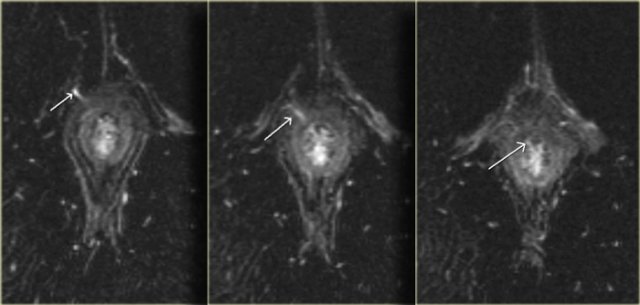

This patient was already known to have an intersfincteric fistula, the mucosal defect is at 1 o'clock.

In the tract there is a linear structure with a low signal intensity.

This is the Seton which was inserted to treat the fistula.